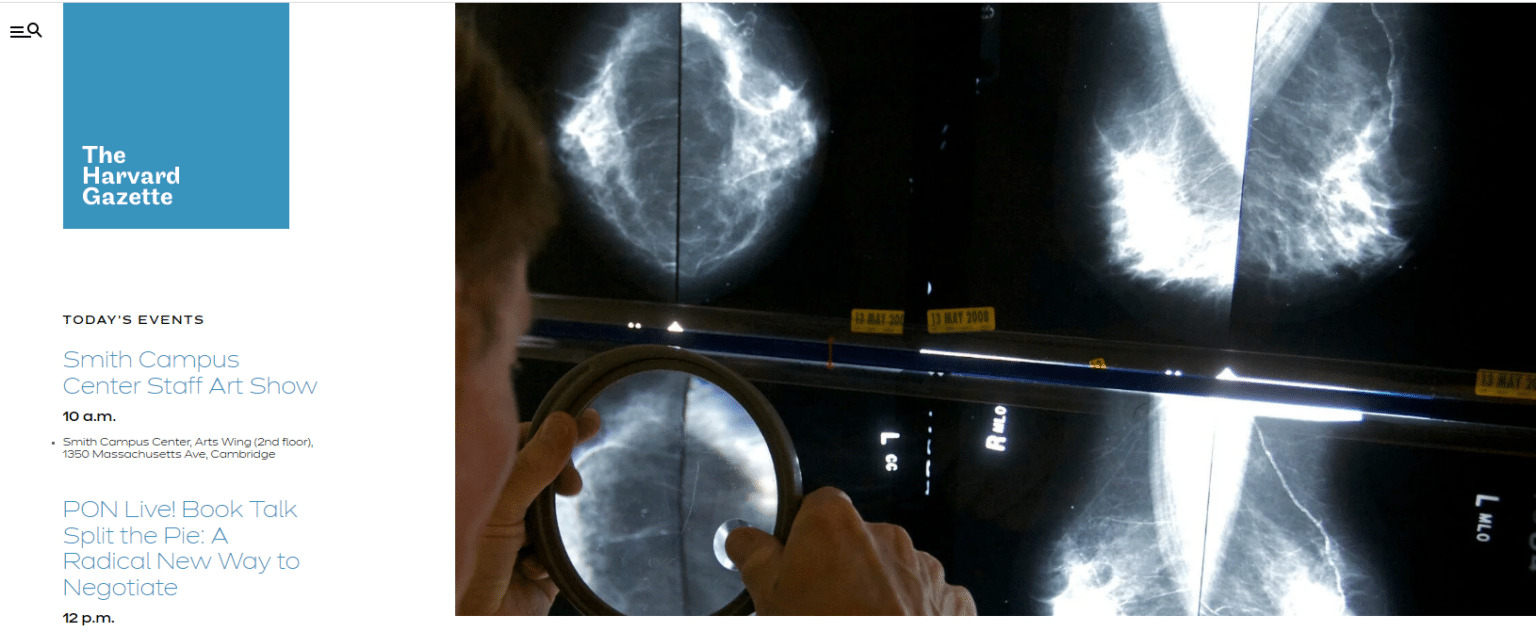

10. The Harvard Gazette

Không chỉ sử dụng để thiết kế website giới thiệu hay bán hàng thông thường mà WordPress còn được tận dụng để xây dựng trang web dành cho các trường đại học. Tiêu biểu trong số đó, Havard University đã sử dụng nền tảng này để tạo ra trang The Havard Gazette. Đây là một blog tin tức chính thống được sử dụng để cập nhật các thông tin về giảng dạy, nghiên cứu, sự kiện,… của trường.